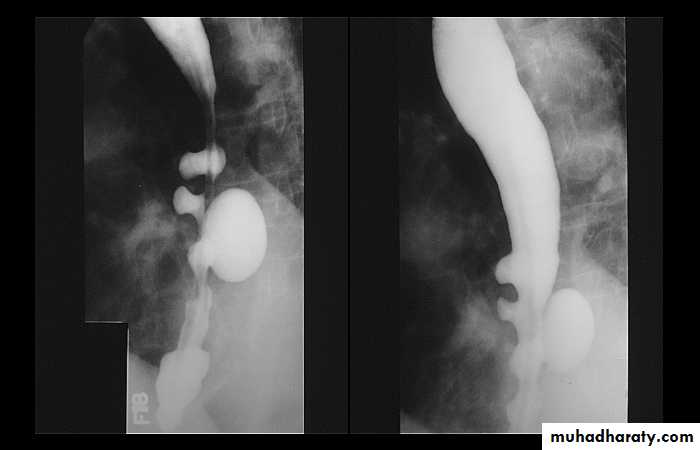

Sliding herniaOn the left initially, GE junction is below the esophageal hiatus. Later, stomach protrudes through hiatus

Para esophageal hernia

On the far left gas filled gastric funds (asterisk) protrudes through hiatus but GE junction (arrow) is below diaphragm• Thin mucosal fold (membrane)